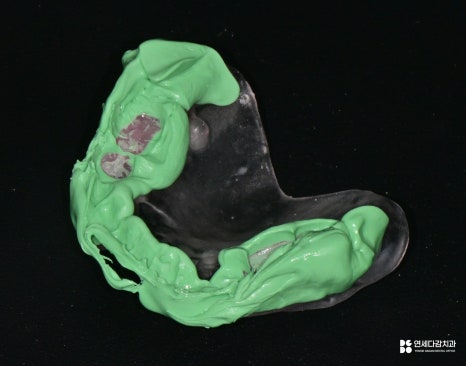

먼저 환자의 구강을 정확히 인상 채득하여

Radiographic template라는 장치를 제작합니다.

환자가 교합을 물었을 때

기준이 되는 교합이 일정하지 않아

정확한 위치로 가이드를 설계하기 어려워,

안정적인 교합을 물릴 수 있도록

임시 기준을 만드는 장치라고 이해하시면 됩니다.

개인 구강에 맞춘 가이드 제작

이후 구강 내 시적하여

정확한 교합 관계를 기록하기 위해

바이트 채득 과정을 진행합니다.

그리고 Radiographic template를 착용한 상태에서

다시 한번 CT 촬영을 진행하게 됩니다.

이때 촬영된 CT 데이터는

가이드 제작을 위한 자료로 활용되며

환자 개인 구강에 맞는 수술 가이드가 제작되어

실제 수술 시에 계획된 위치, 방향 그대로

임플란트를 식립할 수 있게 됩니다.